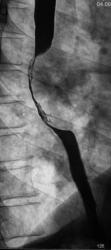

Рентгенограммы и их фрагменты.

По представленным снимкам, у меня сложилось впечатление что пищевод как бы сдавлен извне (овал), возможно образованием в заднем средостении; при этом на довольно продолжительном участке есть нарушение архитектоники складок слизистой с множественными участками barium depletion (стрелки), свидетельствующими в пользу изъязвления.

Исходя из вышесказанного, по данному случаю: сдавление просвета и смещение пищевода мягкотканным образованием, выходяшим за пределы стенки, изъязвление передней стенки пищевода. Заключение: подслизистая опухоль пищевода с изъязвлением, вероятнее всего лейомиома. Рекомендации: эндоУЗИ с биопсией, КТ.

После проведенного рентгенологического исследования органов грудной полости - рентгенографии и томографии, при которой были выявлены увеличенные лимфатические узлы в корнях лёгких и средостении, было проведено рентгенотелевидение пищевода с прицельной рентгенографией и исследованием пищевода на трохоскопе, с контрастированием пищевода водной взвесью сернокислого бария "различной консистенции" - от сверхжидкого - до пастообразного, для "выяснения состояния" заднего средостения. Была зарегистрирована и документирована "локальная деформация пищевода" на протяжении 9,5 см. с перестройкой структуры "рельфа слизистой оболочки".